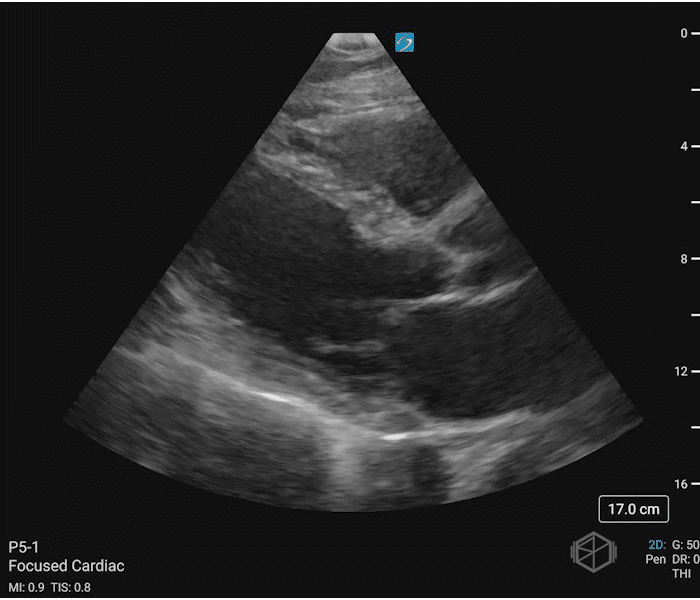

06 - What is the most important clinical finding in this scan?

RV diastolic collapse